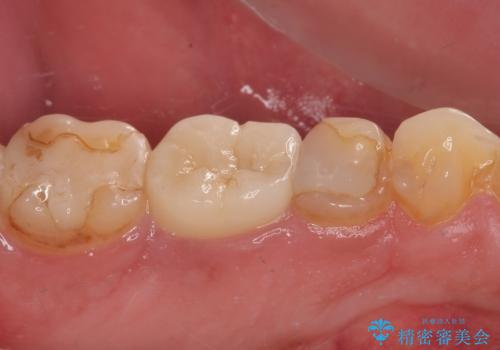

- 奥歯の歯肉から定期的に膿が出てくるとのことで来院された患者様です。

レントゲン写真などの診察を行った結果、根管治療が必要であったため、現在のクラウンを除去し、根管治療を行うこととしました。

根管治療後は症状を確認し、速やかにオールセラミッククラウンにて補綴治療を行うこととしました。